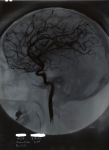

7029 Stéréoscope radiographique - radiographie de profil d'une carotide gauche

7031 Stéréoscope radiographique - radiographie profil carotide gauche à 5 degrés